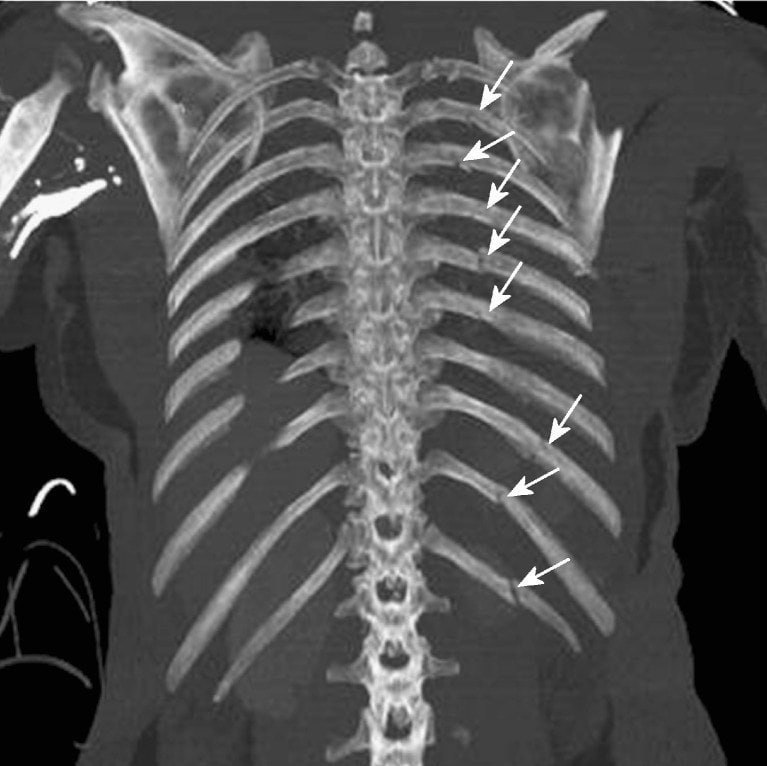

Сломали ребра при реанимации

Сломали ребра при реанимации 112 фото